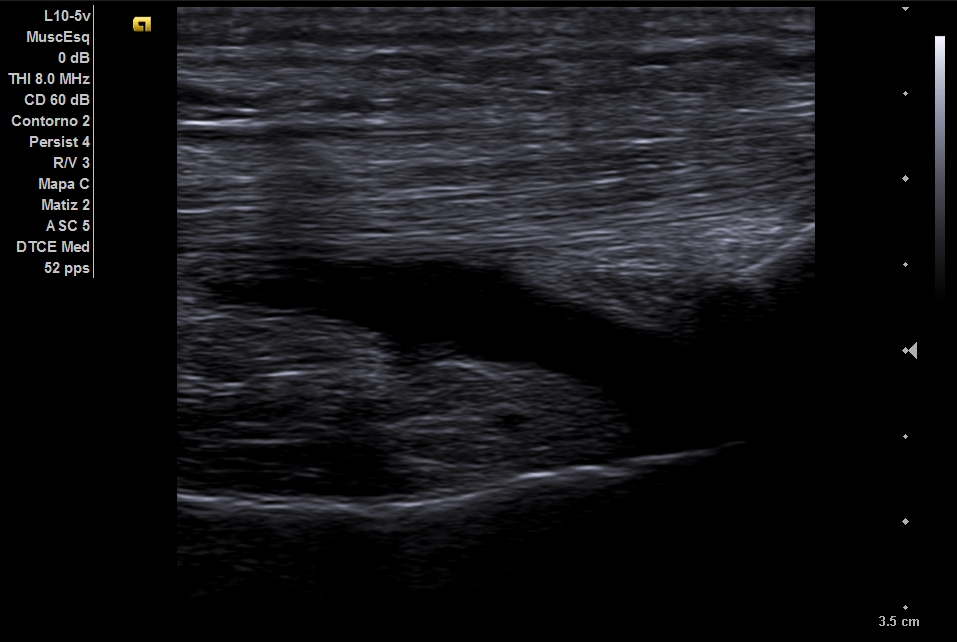

Ecografía de rodilla: imagen anecogénica presanserina sin captación. A nivel de arteria poplítea izquierda se detecta el signo del Yin y Yang.

Ecografía vascular eeii: Placa de ateromatosis poplítea izquierda con elevación de la velocidad pico sistólica (VPS) 133 cm/s, asimétrica respecto a contralateral (55 cm/s).